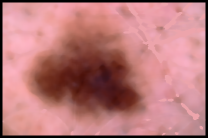

This paper proposes an innovative method for segmentation of skin lesions in dermoscopy images developed by the authors, based on fuzzy classification of pixels and histogram thresholding.

Automated segmentation of skin lesions in dermoscopy images is currently a challenging problem [1]. This paper proposes an innovative method to address this problem developed by the authors. It has been structured as follows. Firstly, in this introduction, on the one hand the segmentation problem is described and, on the other, the evaluation criteria used (image database, ground truths and metrics) are shown. Secondly, the system design is presented. Thirdly, the results and the discussion are shown.